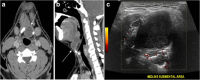

Focal and diffuse thyroid abnormalities are commonly encountered during the interpretation of computed tomography (CT) exams performed for various clinical purposes. These findings can often lead to a diagnostic dilemma, as the CT reflects the nonspecific appearances. Ultrasound (US) examination has a superior spatial resolution and is considered the modality of choice for thyroid evaluation. Nevertheless, CT detects incidental thyroid nodules (ITNs) and plays an important role in the evaluation of thyroid cancer. In this pictorial review, we cover a wide spectrum of common and uncommon, incidental and non-incidental thyroid findings from CT scans. We also discuss the most common incidental thyroid findings, best practices for their evaluation, and recommendations for their management. In addition, we explore the role of imaging in the assessment of thyroid carcinoma (before and after treatment) and preoperative thyroid goiter, as well as localization of ectopic and congenital thyroid tissue.

Teaching points: • Thyroid disorders tend to have non-specific CT appearances. • ITNs are common on neck CT. • ITN management depends on nodule size, age, health status, lymphadenopathy, and invasion. • CT is used in assessment of cancer extension, mass effect, invasion, and recurrence. • CT plays a role in preoperative planning in patients with symptomatic goiter.